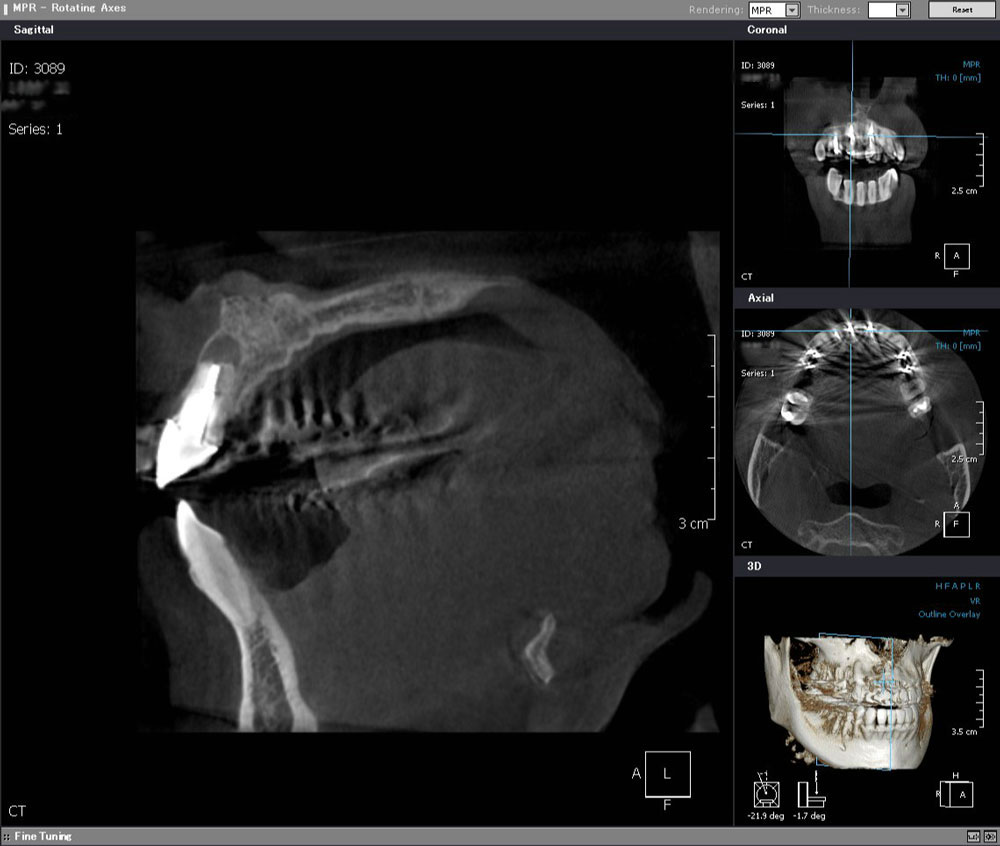

術前CT

過去に歯根端切除を受けた形跡を認めるが、完治せず根っこの先に黒い境界明瞭な骨透過像を認める。